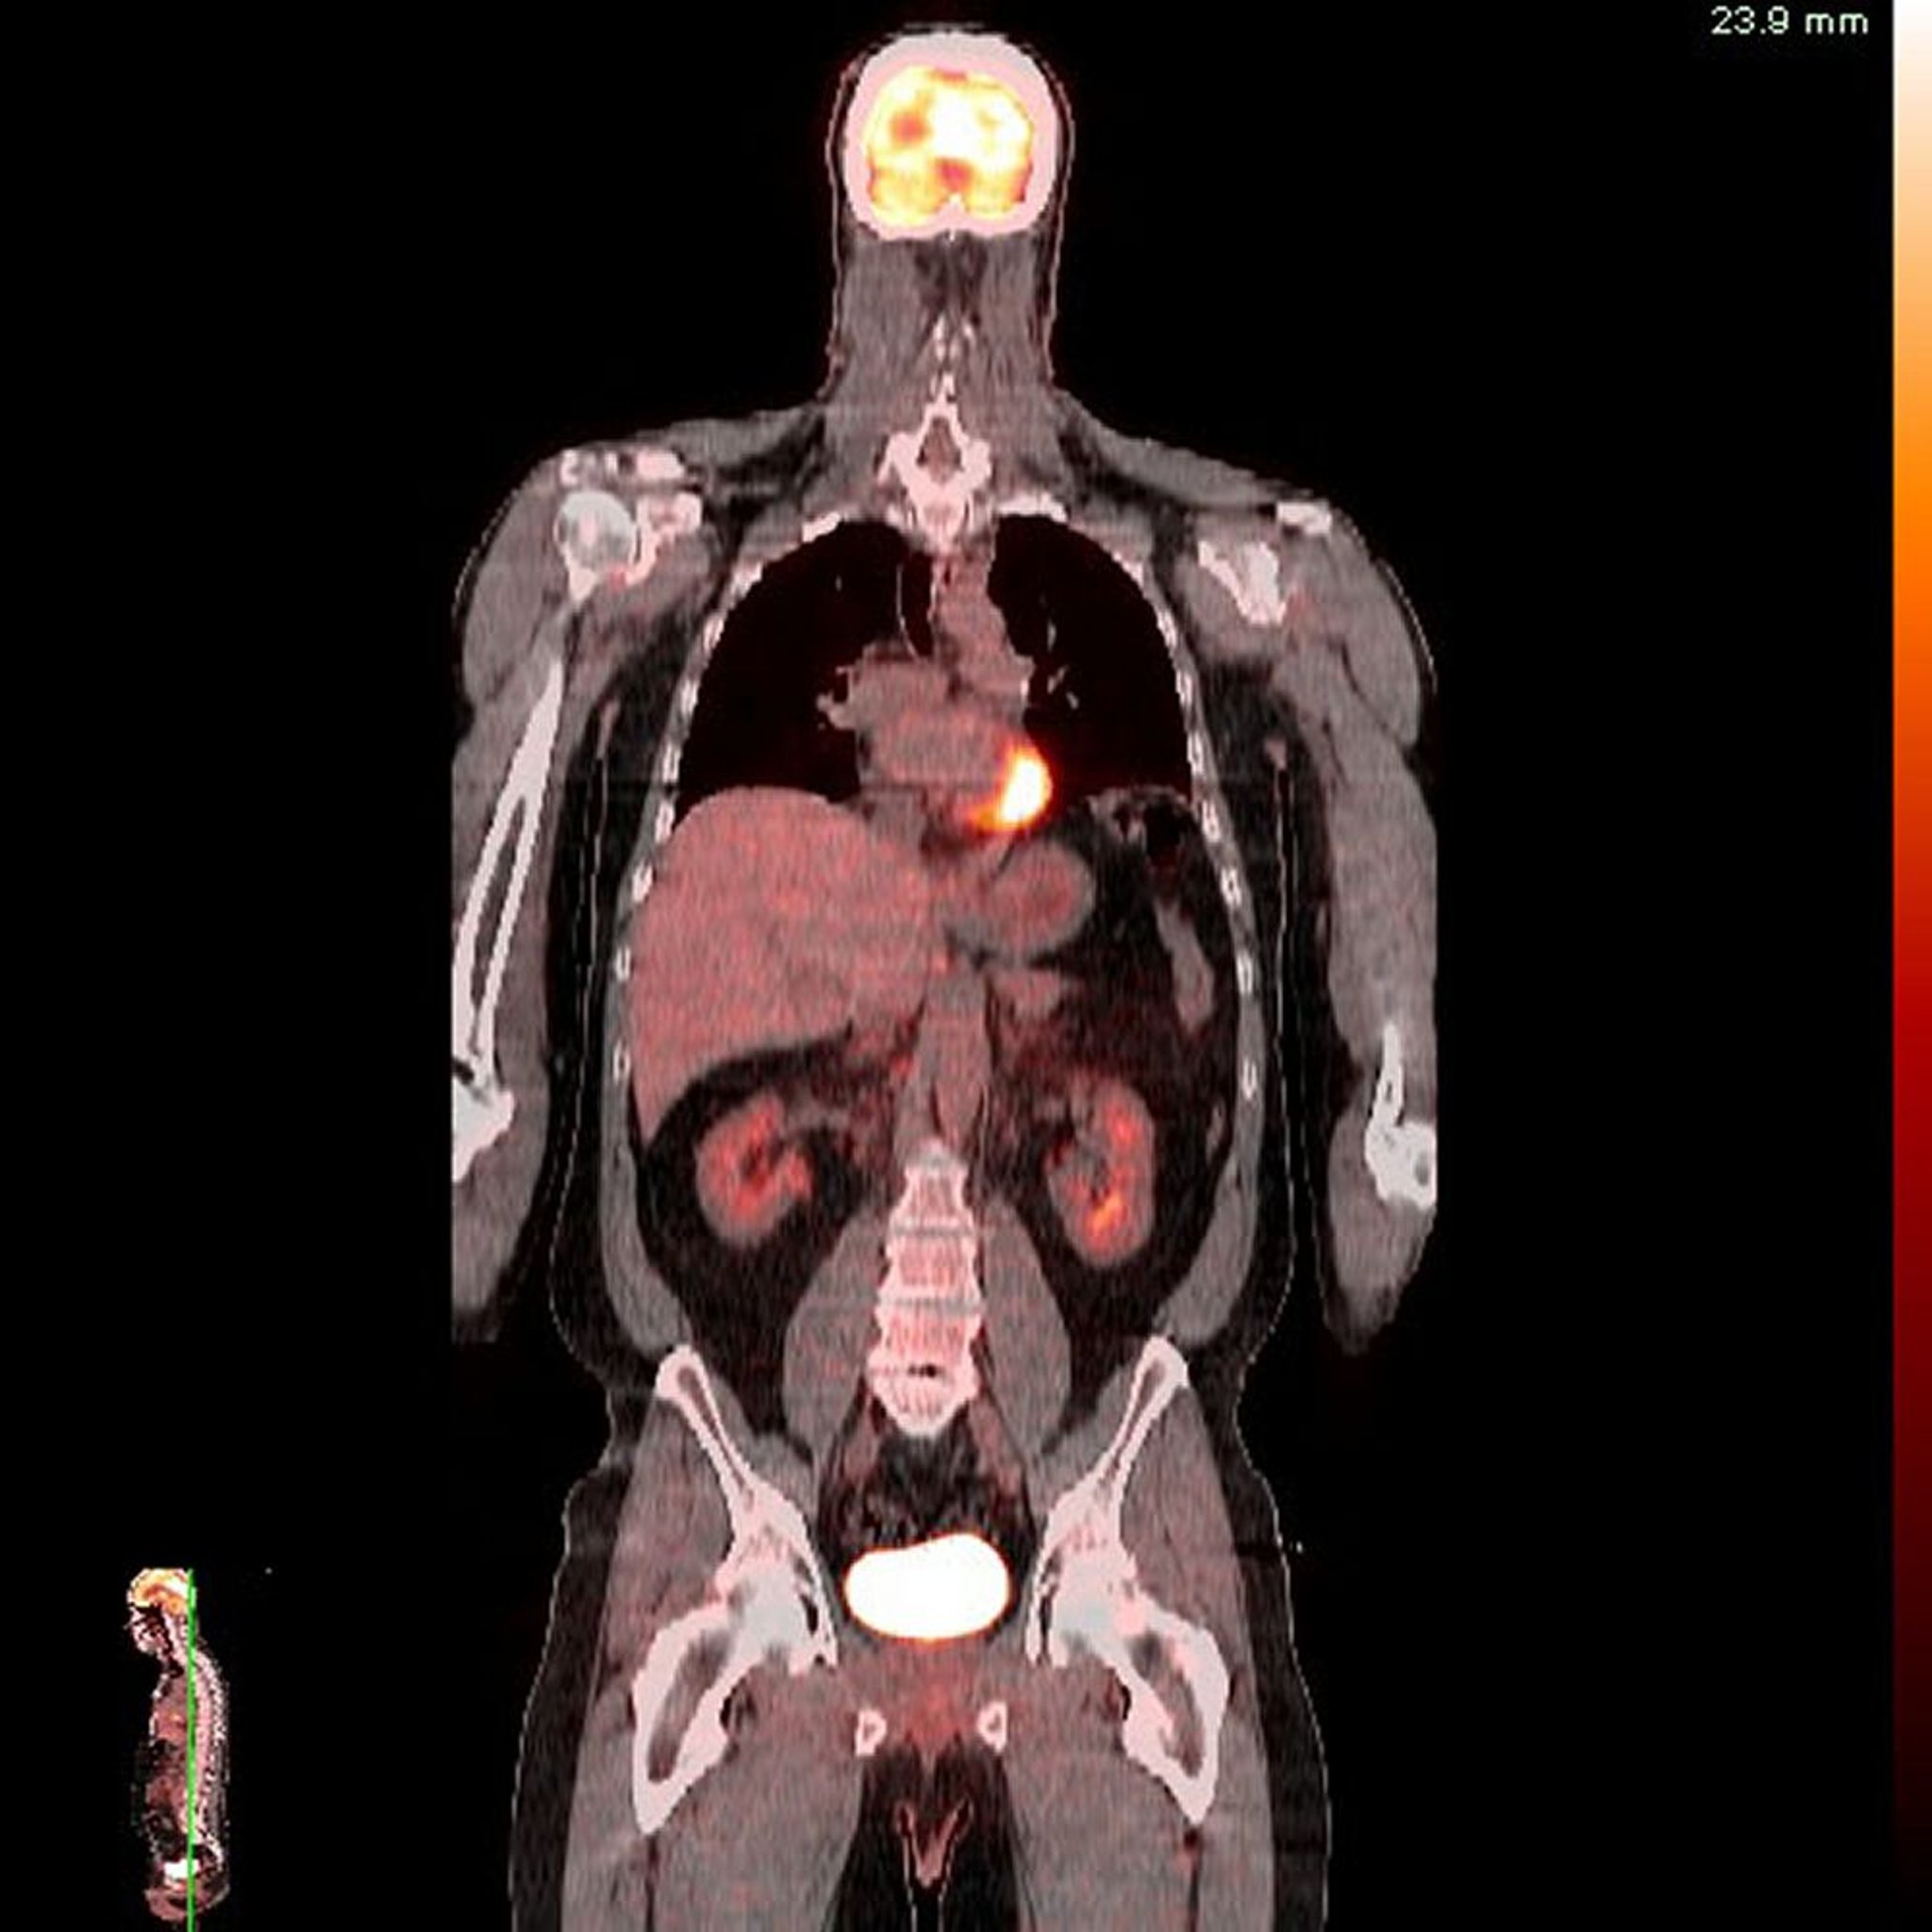

양전자 방출 단층촬영-컴퓨터 단층촬영(PET-CT)

이미지 제공: Jon A. Jacobson, MD.